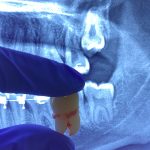

Selain usia, ada beberapa tanda-tanda yang menunjukkan bahwa anak perlu dibawa ke dokter gigi lebih awal. Misalnya, jika anak sering mengalami rasa sakit atau tidak nyaman di mulut, memiliki bau napas yang tidak sedap, atau gigi mereka tampak berubah warna atau terlihat rusak.

Jika kamu melihat tanda-tanda ini pada anakmu, jangan ragu untuk membuat janji temu dengan dokter gigi untuk mendapatkan penilaian lebih lanjut.